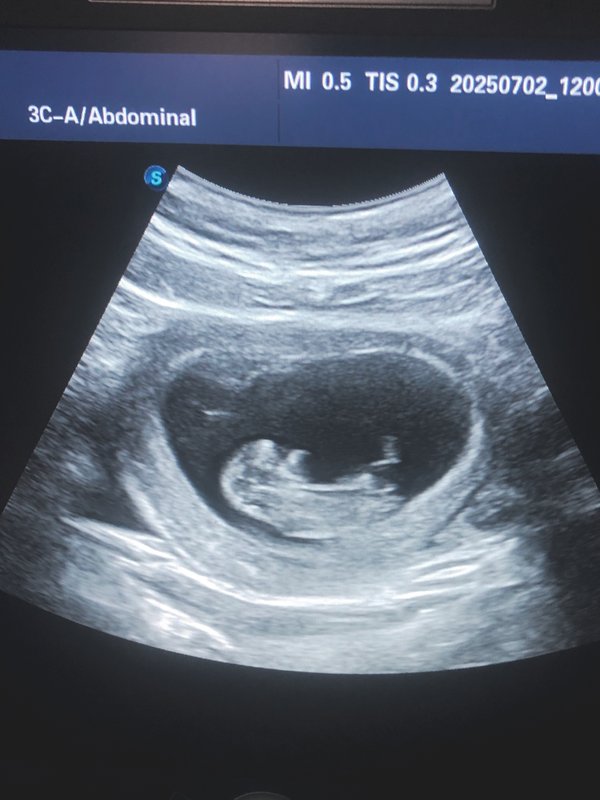

Бородулина Наталья (Врач УЗИ, Косметология) (12.05.2025): Для наилучшего визуального изображения малыша лучше всего делать на сроке с 17- й по 33- ю неделю беременности. Оптимальное время — 20–28 недель. ‼️На начальных сроках (до 10 недель) 3D-5D-УЗИ малоинформативно. ️После 30–31-й недели из-за малого количества околоплодных вод объемная картинка может не получиться .

Бородулина Наталья (Врач УЗИ, Косметология) (27.03.2025): #УЗИ беременных: Ваш путь к чуду жизни! Каждый момент ожидания — это удивительное приключение‼️ УЗИ — не только возможность увидеть своего будущего малыша, но и важный шаг в заботе о здоровье вас и вашего ребенка. Что дает УЗИ? — Определение срока #беременности — Мониторинг развития плода — Выявление возможных аномалий — Определение пола ребенка (в некоторых случаях) Преимущества УЗИ: — Безопасно и безболезненно — Позволяет вам увидеть вашего малыша на экране — Возможность записа… — Читать дальше

ть видео или #фото для воспоминаний ️ Не упустите шанс‼️ Запишитесь на УЗИ и подарите себе и вашим близким уникальные эмоции!